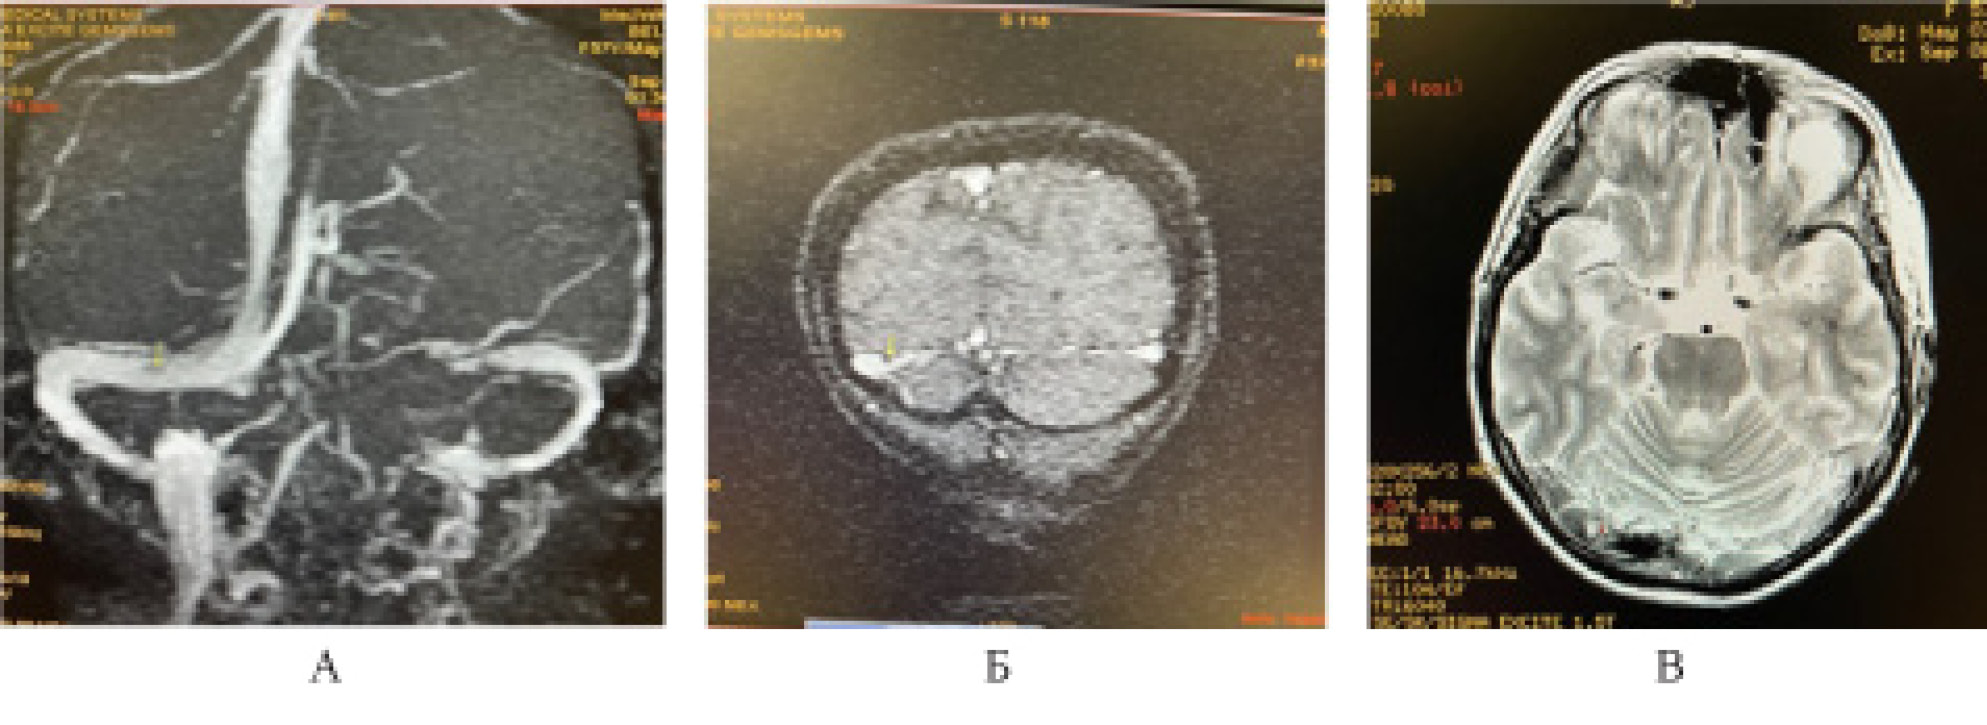

МР-веносинусография головного мозга от 07.09.2021 (рис. 3, 4).

Рис. 3. Магнитно-резонансная венографическая картина: отсутствие сигнала от кровотока по значительной части левого поперечного синуса (А), что не позволяет исключить тромбирование, либо замедление кровотока (Б), с учётом Cor N1 взвешенного изображения

Рис. 4. Магнитно-резонансные венографические признаки, подозрительные на единичный тромб в правом поперечном синусе (А). Однако, с учётом сырых данных (Б) и нативного Т2-взвешенного изображения, эти изменения являются арахноидальными грануляциями, врастающими в синус (В)